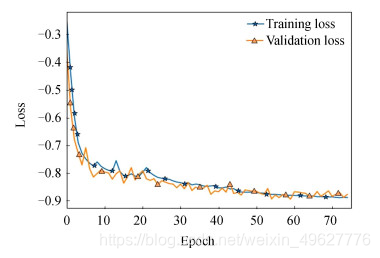

图 9和10分别为结合实例归一化网络收敛示意图和脑肿瘤测试集Dice指标分布图.对比图 7(b)和图 9可知,结合了实列归一化的脑肿瘤检测网络收敛速度更快,训练集和测试集的损失值曲线拟合程度良好,表明实列归一化的方法不仅能够加快网络的收敛速度,同时也缓解了多模态脑肿瘤检测网络中存在的过拟合问题.

图 9 结合实例归一化网络收敛示意图

为验证三维卷积神经网络,将二维检测网络与三维检测网络的实验结果进行了对比,图 16为二维检测网络收敛示意图.

图 16 二维检测网络收敛示意图

对比图 16和12可知,三维检测网络的损失函数收敛拟合程度更佳,二维检测网络的训练和测试损失值为-0.875 9及-0.870 7,而三维检测网络可达到-0.909 4和-0.901 7,分别提升了3.35%和3.1%.